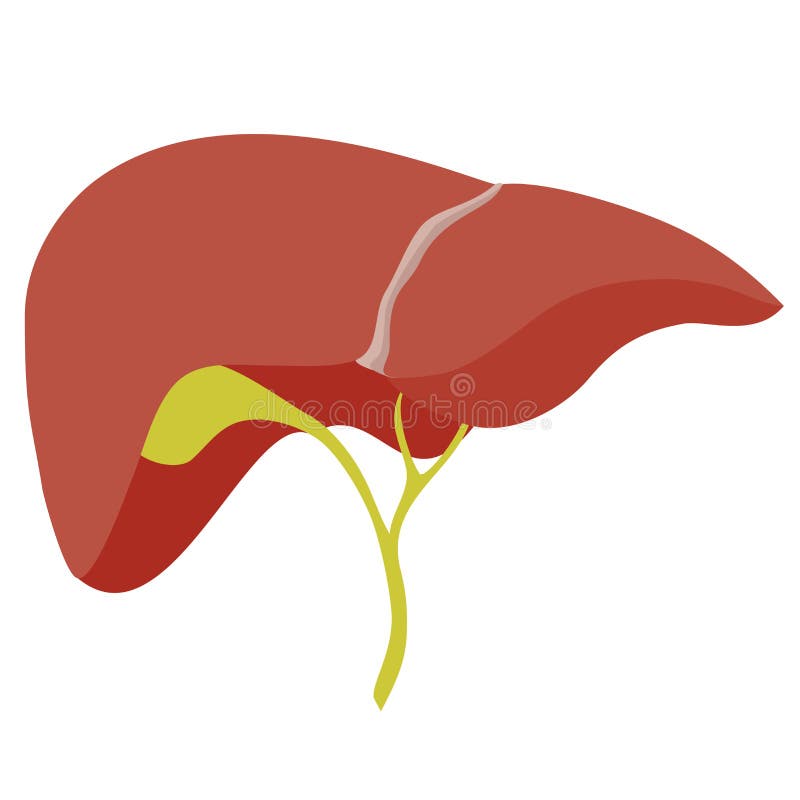

Печень, один из самых крупных и важных органов человеческого тела, выполняет множество жизненно необходимых функций, включая фильтрацию токсинов и производство жизненно важных белков. В данной статье мы рассмотрим, как наглядные изображения печени могут помочь лучше понять её структуру, функции и возможные заболевания. Использование рисунков и диаграмм делает сложные биологические процессы более доступными для понимания, особенно важно это для студентов, врачей и пациентов, стремящихся глубже изучить этот ключевой орган.

Печень рисунок